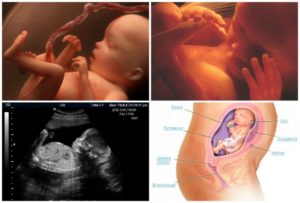

Когда беременность достигла срока 23 недели, ваш малыш весит 607 грамм. Его рост колеблется от 28 до 30 см. Размер плода можно сравнить с кукурузой. Вы можете сравнить снимки первого УЗИ и второго. Впечатляет, как за это время ребенок изменяется, сколько стадий развития он проходит.

Развитие плода на 23 неделе беременности имеет такие показатели: масса 450 — 500 г, а рост — около 26 см.

Малыш весит около полукилограмма и вытянулся до 29 см. Пропорциями он напоминает новорожденного. Его кожа выглядит морщинистой, складчатой, и сквозь нее просвечивают артерии и вены. Это вызвано тем, то прослойка жировой ткани пока недостаточна для размеров его тельца.Активно развивается головной мозг. К 23 неделе беременности формируется и активизируется вестибулярный аппарат, отвечающий за равновесие и координацию движений, моторику тела, способность управлять положением глазных яблок. Двигаясь в полости матки, ребенок стимулирует его развитие, а развитие вестибулярного аппарата, в свою очередь, способствует расширению диапазона движений.

Длина плода в среднем 29-31 см, а вес – целых полкило. Кожа утрачивает прозрачность из-за того, что в ней начинает вырабатываться красящий фермент. Под кожей продолжается активное накопление жира.

Кожа приобретает ярко-красный оттенок, но она пока тонкая и прозрачная, подкожный жир продолжает накапливаться. К концу недели кроха может весить 500 грамм или чуть больше, а длина его тельца составит около 29 см.

Размер и развитие плода

Рост ребенка на 23 неделе беременности увеличивается до 20 см (в положении «сидя»), а масса тела достигает 450 г. Это значит, что за предыдущую неделю малыш подрос на 1 см и поправился на целых 100 г.

С организмом малыша в это время происходят следующие важные изменения:

- кожа выглядит очень сморщенной, так как она растет быстрее, чем накапливается подкожный жир;

- пушок, покрывающий тельце плода, начинает приобретать темный оттенок;

- некоторые исследователи полагают, что на 23 неделе ребенок способен видеть сны;

- глаза у ребенка уже открыты, он прекрасно различает уровень освещенности вокруг себя;

- масса головного мозга плода в этот период внутриутробного развития составляет около 20-25 г;

- начинает активно функционировать селезенка.